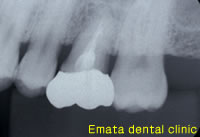

| 成功するか否かは、いかに歯根膜を傷つけずに丁寧に抜歯するか、また移植歯にぴったり歯肉を隙間なくつけるための切開、縫合が重要なポイントです。 | |

| 咬み合わせの強いかたなのでゴールドで被せ物をしました。 | |